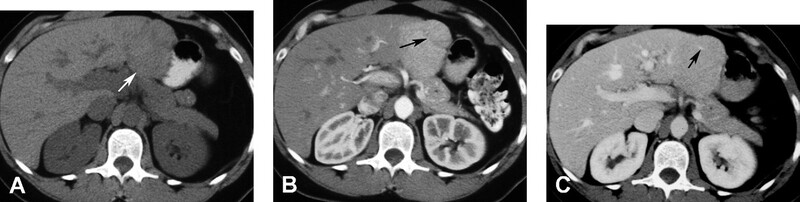

Hình 8. Nữ 38 tuổi có sử dụng thuốc ngừa thai đường uống, với adenoma gan vỡ và máu tụ dưới bao. CT không cản quang (A) thấy xuất huyết nội (mũi tên đen) bên trong adenoma và máu tụ dưới bao (mũi tên trắng). Thìđộng mạch (B) thấy bắt quang (mũi tên) phần đặc, thải thuốc và trở nên đồng đậm độ với gan ở thì tĩnh mạch cửa (C). Có vỡ u (mũi tên) ở phía ngoại vi với máu tụ dưới bao.

Trên CT không cản quang, HCC thường giảm đậm độ so với gan. HCC bắt quang thì động mạch và trở nên giảm đậm độ ở thì tĩnh mạch cửa (Hình 10). Viền bắt quang mỏng có thế có ở thì tĩnh mạch và thì muộn do giả bao. Thực hiện thì động mạch trễ (34 giây) đã được báo cáo cho thấy các nốt HCC hơn thì động mạch sớm (20 giây). Các hình thì động mạch sớm có khả năng chụp mạch CT 3D chất ợng tốt hơn để lập bản đồ mạch máu trước phẫu thuật. Thêm hình ảnh CT thì muộn (180 giây) đã được báo cáo để cải thiện độ nhạy và độ đặc hiệu trong phát hiện HCC so với CT hai pha.

Hình 10. Bệnh nhân nam 62 tuổi xơ gan và carcinoma tế bào gan thâm nhiễm lan tỏa. CT không cản quang (A) thấy bờ ngoài gan dạng nốt kèm khối giảm đậm độ (mũi tên) ở thùy gan phải. CT thì độn g mạch (B) thấy khối bắt quang không đồng nhất (mũi tên). Huyết khối do u bắt quang không đồng nhất (mũi tên ở C) làm phình lớn tĩnh mạch cửa và lan đến chỗ hợp lưu tĩnh mạch mạc treo tràng trên (mũi tên ở D). U đồng đậm độ (mũi tên) với gan do thải thuốc ở thì tĩnh mạch cửa (E).